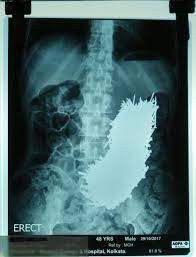

Hasil usg yang menunjukkan banyak paku bersarang di perut (banjarmasin.tribunnews.com)

"Kami memotong sebagian perutnya dan menggunakan magnet untuk mengeluarkan paku satu per satu. Ada lebih dari 600 paku di dalamnya. Dipastikan semua paku yang dia telan, dikeluarkan," tambahnya.

600 paku yang berhasil dikeluarkan saat operasi (kumparan.com)